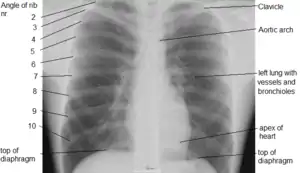

A chest radiograph with the angle parts of the ribs and some other landmarks labeled.

این رادیوگرافی نمای خلفی قدامی (PA) قفسه سینه است یعنی برای گرفتن آن کلیشه رادیوگرافی در جلوی قفسه سینه قرار گرفته و امواج اشعه ایکس از پشت تابیده میشود و بیمار ایستاده است.